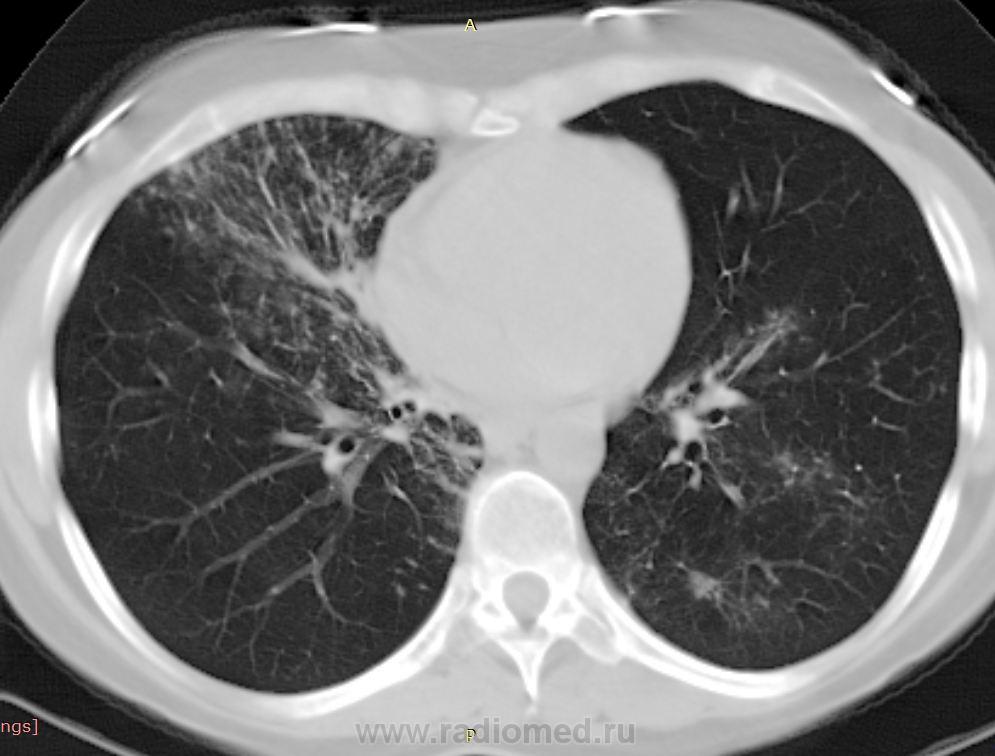

38 лет. 6 лет назад cr носоглотки. Лучевая и химиотерапия. С июля 2012 г. клиника бронхолегочного заболевания.

Срезы по 5 и 7 мм - не лучший вариант для интерпретации интерстициальных диффузных заболеваний. В сканах по 5 мм пропущена центральная часть исследования.

Узелки хаотичного распределения (туб, микозы, мтс). Участки, напоминающие дерево-в-почках. На верхушках посттуберкулезный фиброз, при этом верхние отделы, насколько можно судить, чистые. Прикорневой фиброз и тракционные бронхоэктазы нижних отделов. Преобладание процесса в нижних долях + фиброзные изменения, +  утолщение??? междолькового интерстиция. Значимой лимфаденопатии не нашла, выпота тоже.

На первое место - неспецифическая интерстициальная пневмония. Спецпневмофиброз верхушек. Насколько возможна реактивация туберкулеза прогнозировать не берусь.

Присоединюсь к ЛГ (со всеми ее оговорками): ДИЗЛ, неспецифическая интерстициальная пневония, участки фиброза, бронхиолита.

Хотелось бы увидеть КТ в другом окне. По-моему, за онко ничего нет, больше всего склоняюсь к саркоидозу. Обширность поражения от верхушек к куполам. Да и участки фиброза в верхушках видел неоднократно, писали , что ТБЦ, а оказывалось саркоидозом. Единственно, смущают бронхоэктазы.